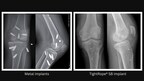

Arthrex, a global leader in minimally invasive surgical technology, announced that it has released the TightRope® SB implant, the first device on the market for anterior cruciate ligament (ACL)...